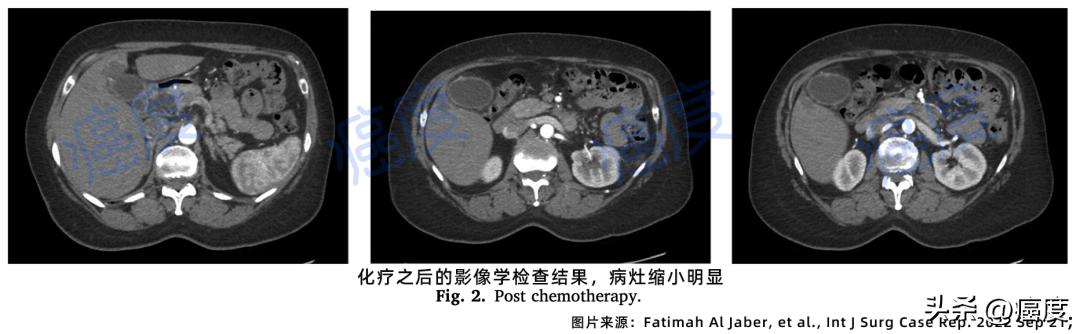

经过左侧肝部的病灶活检,再次证实肝部病灶是胆囊转移病灶。由于转移到了肝部,暂时无法进行手术治疗。经过多学科会诊后进行了姑息性化疗,接受了六个周期的吉西他滨联合顺铂,患者对化疗的耐受性很好,肿瘤标志物逐渐恢复正常。影像学检查显示胆囊肿块也在缩小。

图2.化疗之后的肿瘤病灶显著缩小